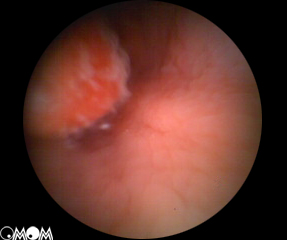

胃息肉胃息肉很少有陽性體徵,合併炎症時上腹部可有壓痛,出血多者有繼發性貧血表現。X線胃鋇餐透視和胃鏡檢查是診斷胃息肉的主要方法。X線胃鋇餐透視顯示胃腔內呈現圓形或半圓形邊界整齊清晰,表面平整的充盈缺損,多數在1cm左右大小,有蒂者可見其移動。胃鏡檢查對診斷實屬必要,鏡下可見胃壁黏膜上有圓形或半圓形隆,一般小於2cm。邊界清晰,表面光滑平整,色澤呈正常黏膜象或呈鮮紅色,質地柔軟,有蒂或無蒂,單發或多發。部分息肉呈菜花狀表現,其表面或有糜爛或有潰瘍。菜花狀息肉和體積大於2cm者有惡變之可能,活組織病理檢查有助於鑑別診斷。